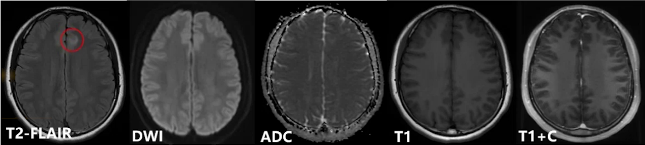

影像学检查方面,头颅MRI平扫显示,在FLAIR序列上,右侧颞叶、左侧海马旁回及左侧额叶均有病灶,呈T2-FLAIR高信号、T2稍高信号,病变位于皮层及近皮层区域。

综合影像分析及临床特点补充,影像学诊断为多发性硬化。回顾病灶特点,颅内病灶多发,经典部位在脑室周围,也可位于皮质及近皮质区域,脑室周围可表现为直角脱髓鞘病灶、Dawson手指征及卵圆形,T2和T2 FLAIR高信号,增强扫描可强化;髓内病灶位于侧索,局灶性、短节段,T2高信号,急性期有强化。临床特殊检查结果显示血的AQP4阴性,脑脊液的寡克隆区带阳性,最终临床结合病史及检查,诊断为复发缓解型多发性硬化。